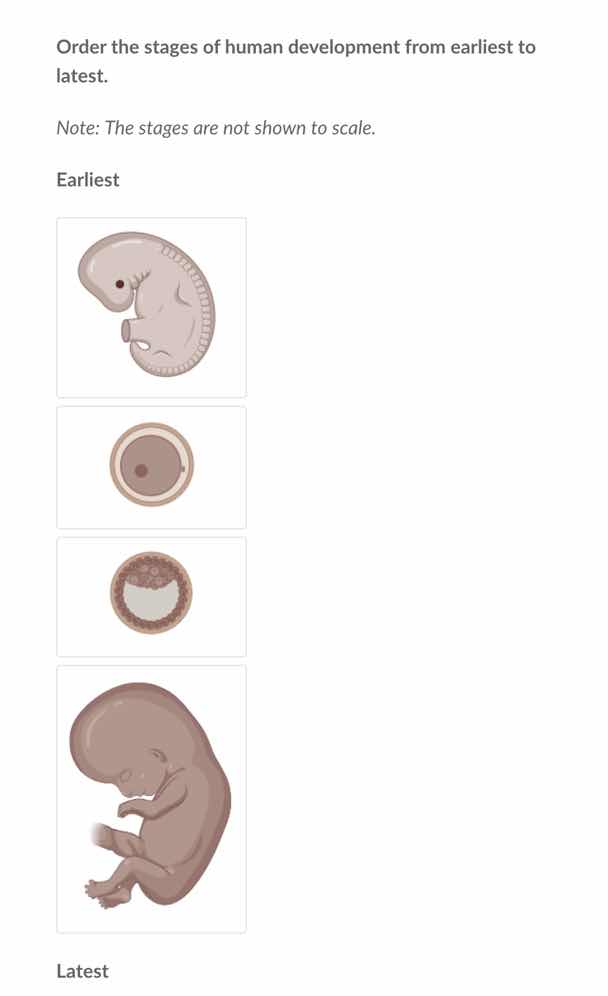

order the stages of human development from earliest to latest.

note: the stages are not shown to scale.

To order the stages of human development from earliest to latest, we analyze the stages:

- The second image (a single - celled or early embryo stage, likely the zygote or early blastocyst precursor) represents the earliest stage as it is the initial form after fertilization.

- The third image (a blastocyst - like structure with a cavity) comes next as it is the stage after the zygote has undergone cell division and formed a blastocyst.

- The first image (an embryo with early body structures) is the next stage as the blastocyst implants and develops into an embryo with recognizable features.

- The fourth image (a more developed fetus) is the latest stage as it shows a more mature form of the developing human.

- Second image (the circular structure with a dot in the center, representing the zygote/early embryo)

- Third image (the circular structure with a cavity and cells around, representing the blastocyst)

- First image (the embryo - like structure with early body features)

- Fourth image (the more developed fetus - like structure)